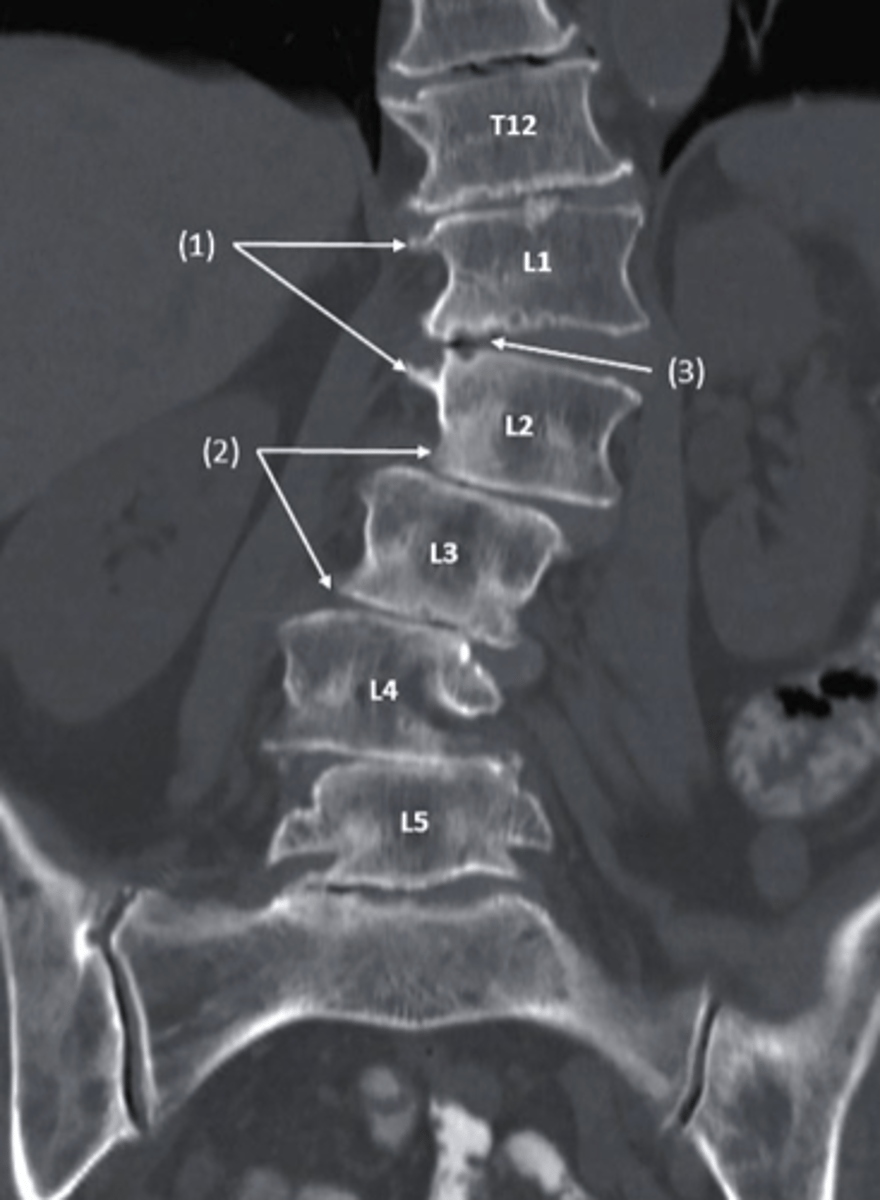

CT scan

what type of imaging is this?

a. T2 MRI

b. Bone Scan

c. CT scan

d. conventional radiography